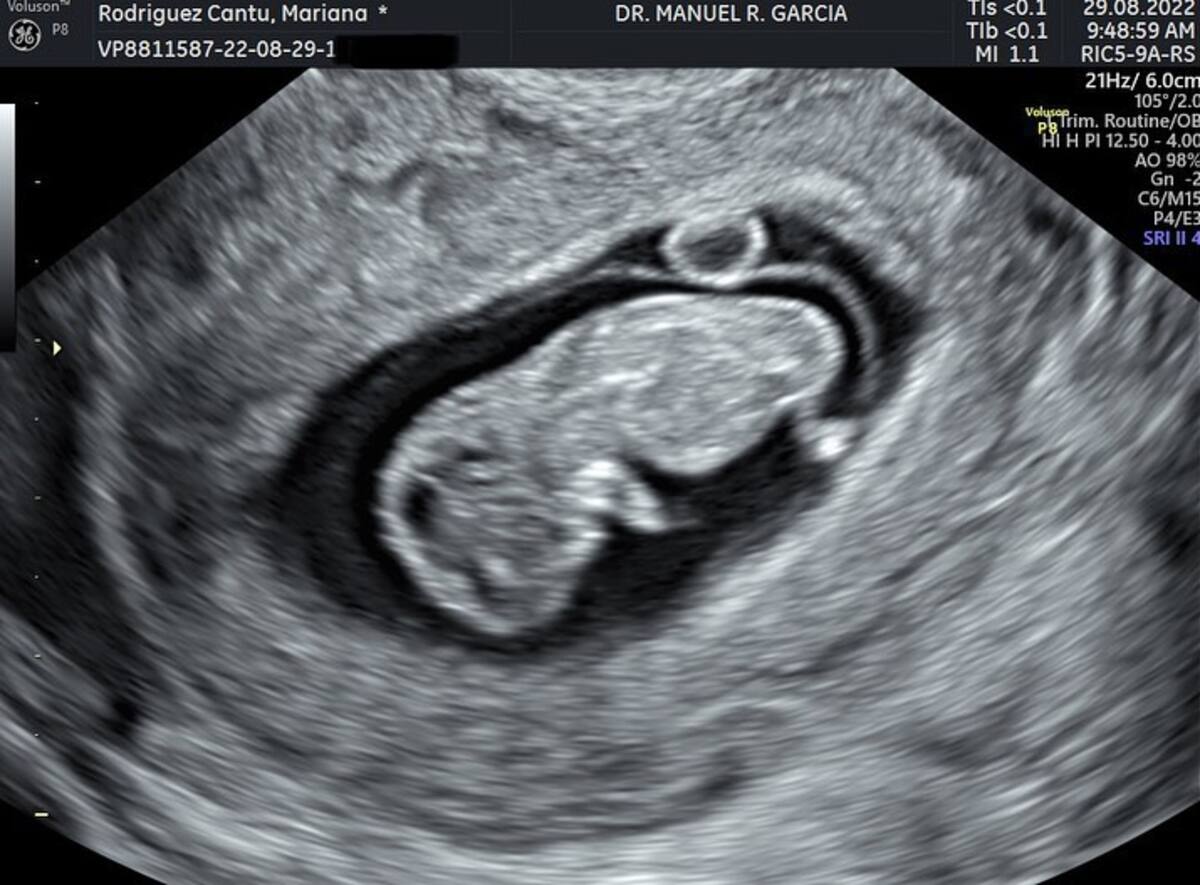

La empresaria e influencer compartió una fotografía en su cuenta de Instagram donde su esposo aparece mostrando su celular con la fotografía del ultrasonido de su primogénito.

En la instantánea se alcanza a distinguir el feto de su bebé y que el ultrasonido se lo hizo minutos antes de darle a conocer al mundo la llegada de su pequeño.